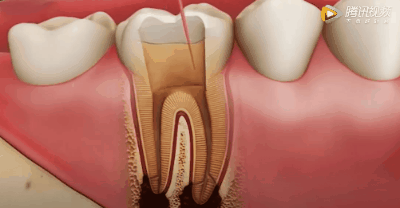

但是,即便牙齿有着这么“坚固的外表”,但它也有着一颗“柔软的内心”——牙齿里面分布着许多的血管和神经,我们将这些组织存在的部位称之为“牙髓腔”。

牙齿剖面图

牙髓腔里面布满了神经,神经末梢在牙齿里面分布的非常丰富,一旦“蛀牙洞”突破到牙髓腔,就会觉得牙齿非常非常疼了。